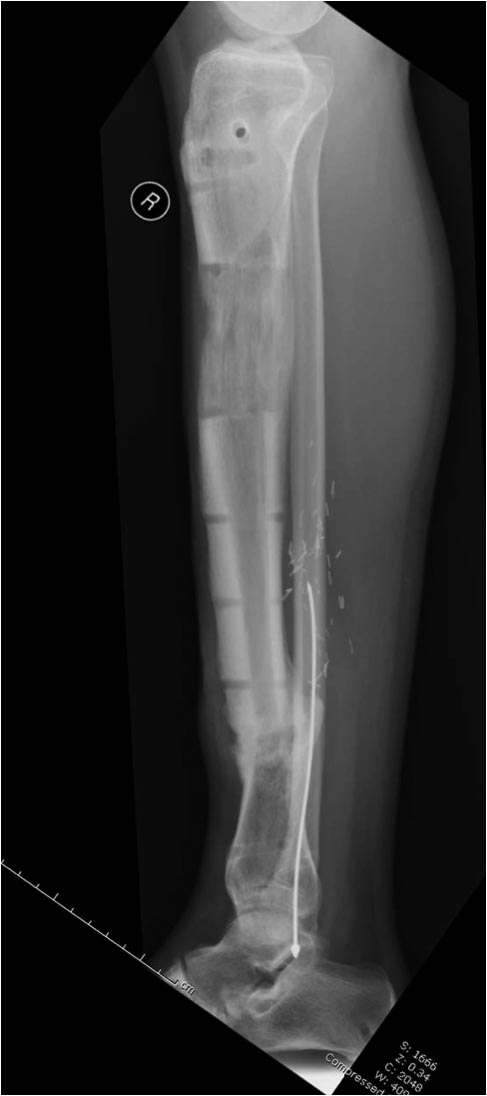

Данный случай не огнестрельная рана, а результат мотоциклетной аварии.

Независимо от повреждения при таких обширных дефектах мягких и костной

тканей применяется схожая тактика. Как видно, после нескольких I&D для

создания “pseudo membrane” применили цилиндрический блок из цемента.

Дефект мягких тканей закрыли свободным Anterior Thigh Graft. Из малого

доступа цилиндр удален небольшими кусочками, а пространство заполнили

бусами для освобождения пространства. По мере приближения регенерата

освободили пространство удалением бус через небольшой разрез. Этап

созревание регенерата можно было ускорить усилением интрамедуллярным

гвоздем, но решили закончить методом Илизарова.